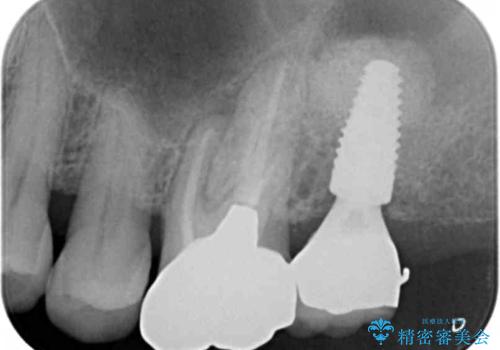

奥歯(左上7)のメタルインレー(銀の詰め物)を除去し精査したところ、奥歯はわれていました。

根尖近くまで深くヒビが入っており保存不可能な状態でした。

患者様のご希望により抜歯してインプラントによる治療を行いました。

上顎洞が近接しており上顎骨の厚みが薄いことから、ソケットリフト(上顎洞底挙上術)をインプラント埋入と同時に行いました。

初診時から治療終了時までのレントゲンをお見せして説明差し上げたところ、「お~!骨ができている!」と喜んで下さいました。

ソケットリフトにより上顎洞底を挙上し骨造成することにより、骨の厚みが薄い部分でもインプラントが可能になります。

インプラントの種類:ストローマン BLT